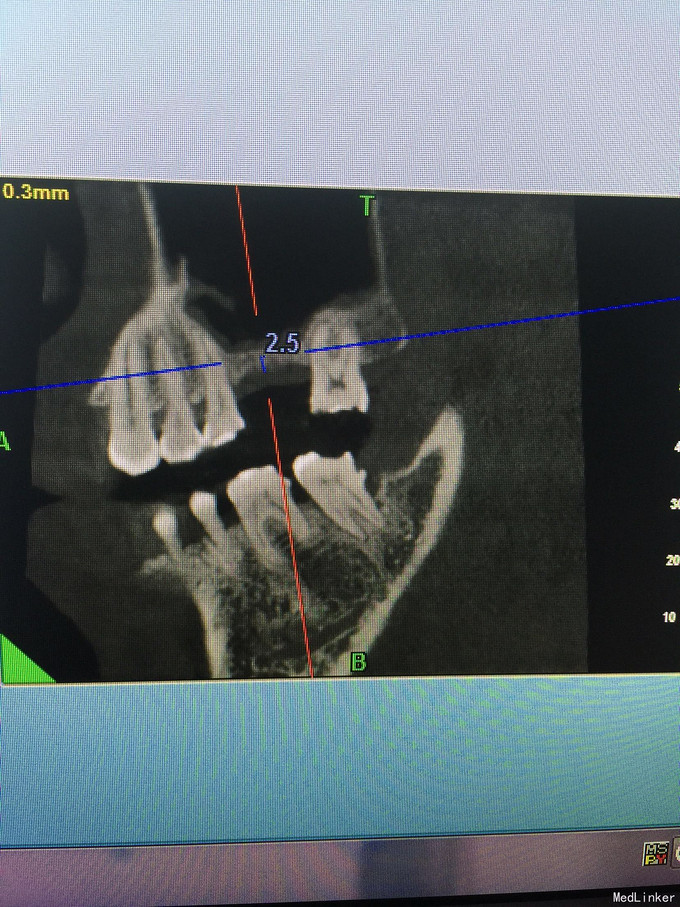

张先生,右上6缺失多年,要求种植

骨量只有2.4毫米

上颌窦内提,同期植入4.1-10植体